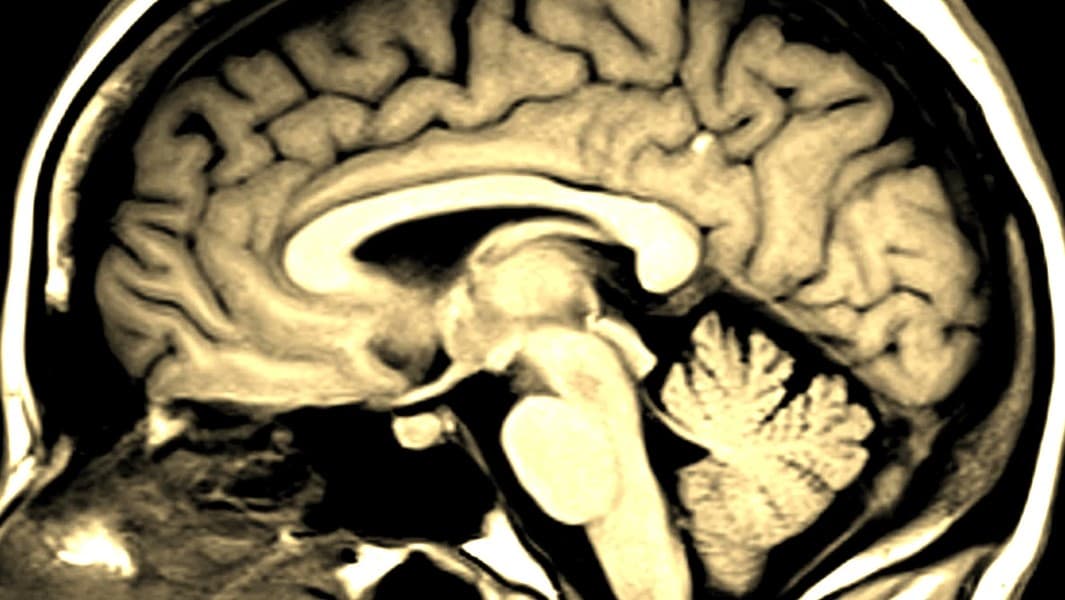

Austin, TEXAS - ¿Sabías que cada 40 segundos una persona en Estados Unidos tiene un derrame cerebral? Mientras que cada 3 minutos con 14 segundos una persona muere a causa de un derrame, según el Centro de Control y Prevención de Enfermedades (CDC). Pero, ¿qué lo causa y cuáles son algunos de los síntomas?¿Cómo puede una persona detectarlo y saber cuándo tiene que ir al doctor?

En el mes de la concientización por derrames cerebrales, experto explica cómo notarlos y qué hacer para evitarlos

Estadísticas revelan que cada año más de 700,000 personas sufren de derrames cerebrales.